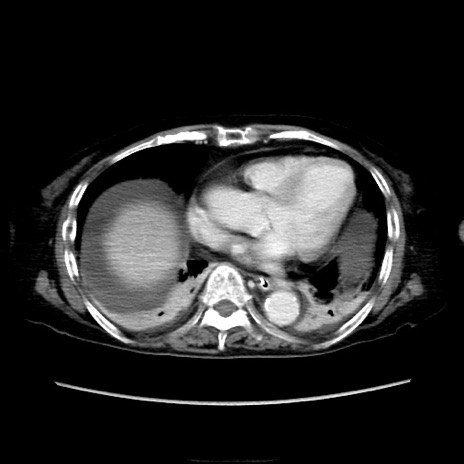

冠状断像